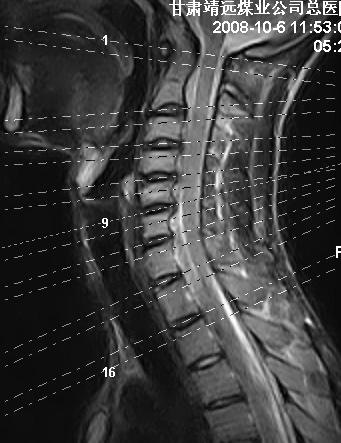

标题: MRI1827:颈椎内异常信号,是不是占位。

患者18岁,学生,在玩耍中受伤来检查,患者喜欢打篮球。颈椎内异常信号影,我们考虑占位,但是不像占位,又考虑硬膜囊的增厚,大家关建看颈椎椎管内的那个异常占位信号

考虑 c3-4 c4-5 c5-6椎间盘突出,l3-4 l4-5 l5-s1椎间盘变性

后纵韧带增厚,颈2/3、3/4、4/5、5/6椎间盘变性、突出;椎体有旋转,提示椎小关节有问题;腰椎间盘变性,许莫氏结节。